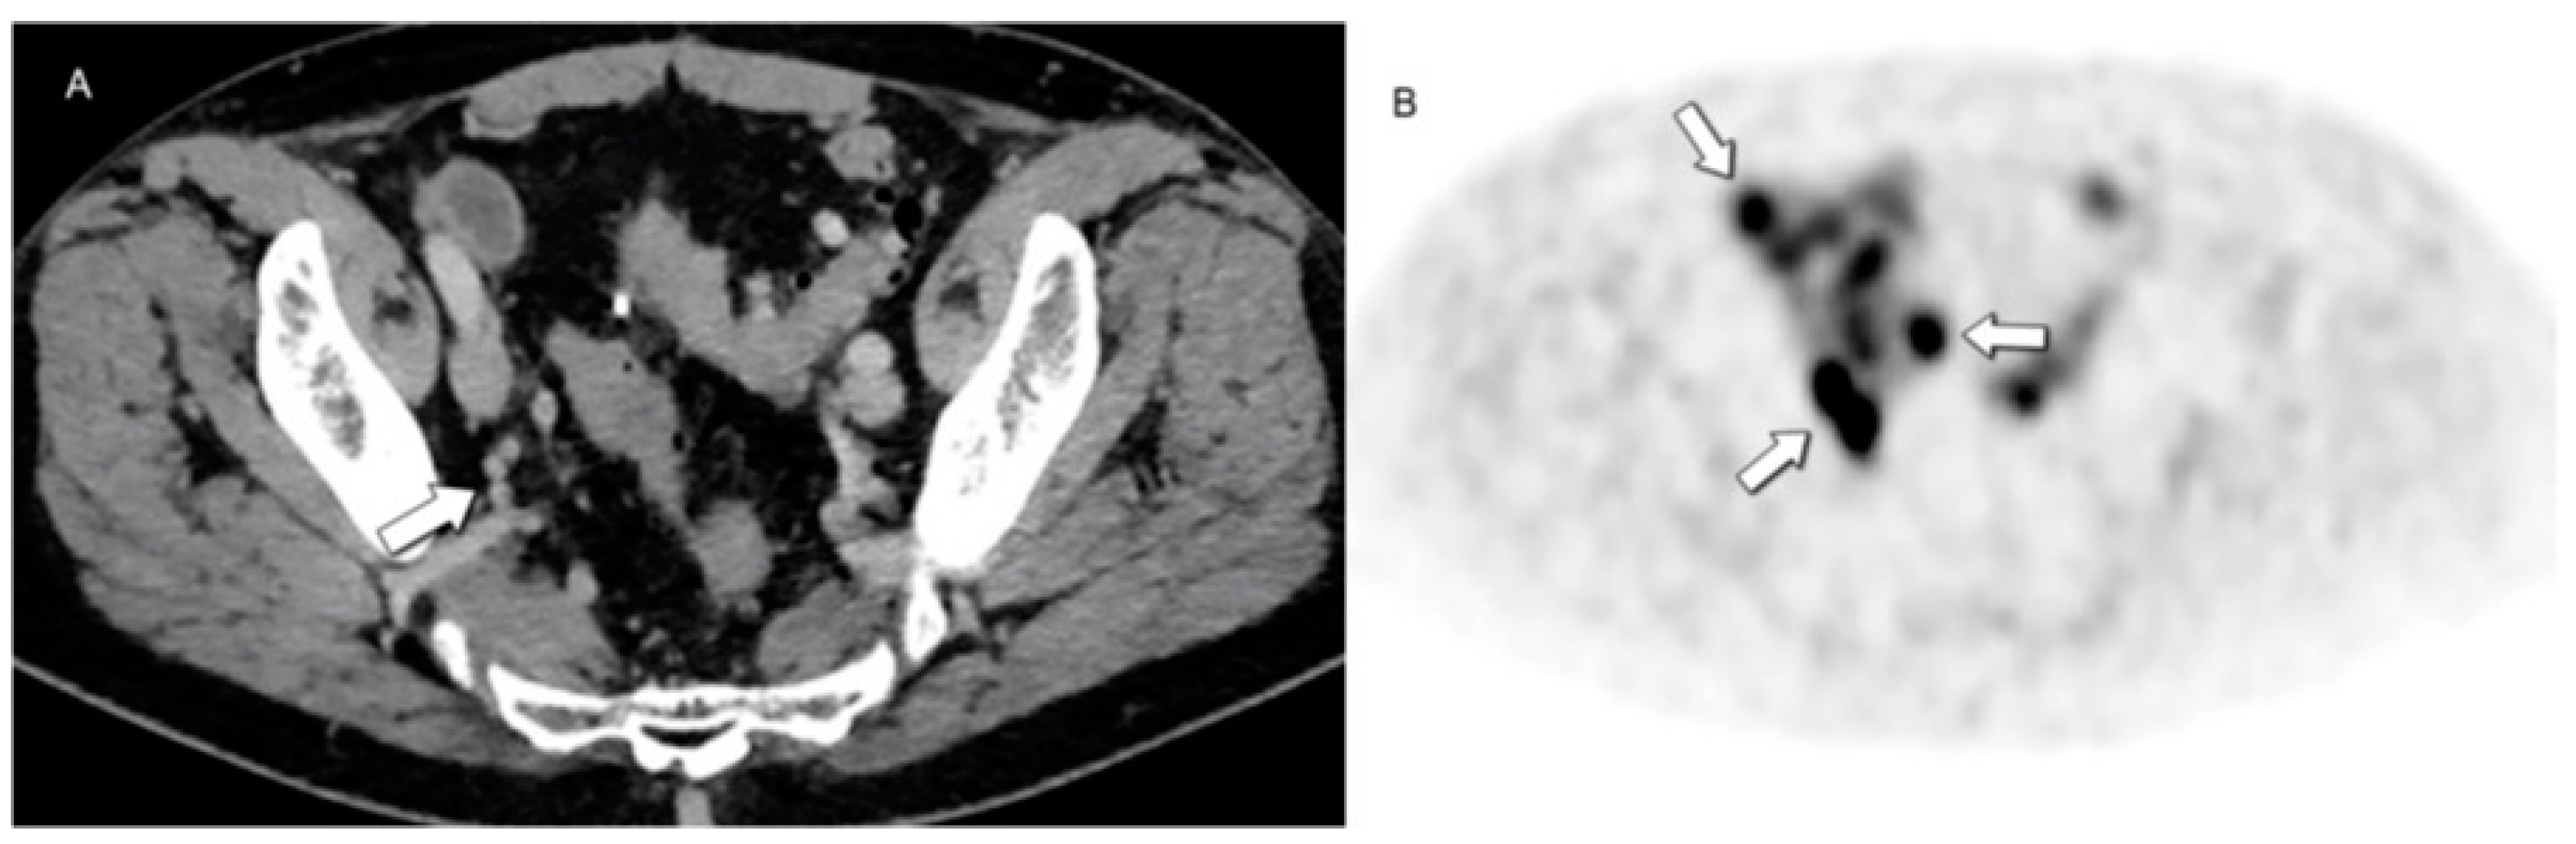

4.2. Hybrid Imaging of NENs